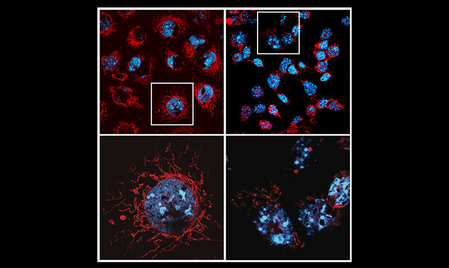

वैज्ञानिक शोध में बड़ा खुलासा, बिल्ली बनी कैंसर रिसर्च की नई कड़ी

कैंसर की दवाओं के साइड इफेक्ट्स की आखिर क्या है वजह? रिसर्च में खुलासा